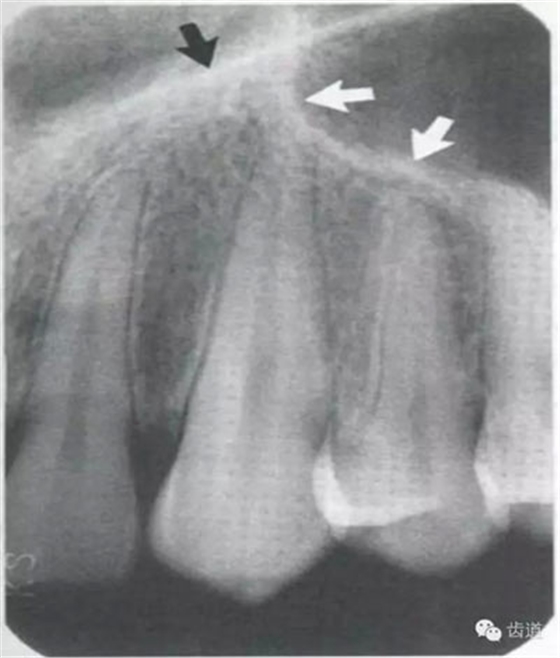

牙頸部Burnout征象:有時(shí)因投照技術(shù)問(wèn)題而造成牙頸部近中或遠(yuǎn)中呈低密度影像,位于牙釉質(zhì)和牙槽嵴頂之間。

在兩個(gè)中切牙牙根之間或稍上方,多呈橢圓形密度低的影像,切牙孔影像可重疊在一側(cè)中切牙牙根尖處,易誤認(rèn)為根尖周病變,可視牙周膜和骨硬板是否完整加以鑒別

位于兩側(cè)中切牙牙根之間,由牙槽突向上,呈直線狀密度低的影像。其兩側(cè)為密度高的影像,為兩側(cè)上頜骨腭突的致密骨層。

鼻腔位于上切牙根尖的上方,顯示為對(duì)稱性半圓形密度低的影像,其中間被一密度高的骨隔分開為鼻中隔